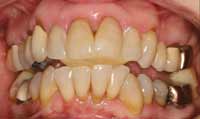

A 57-year-old woman presented with the chief complaints of jaw joint clicking and popping, jaw joint pain, and headaches. She felt that she had a bad bite and that her mouth did not close properly. Further, she disliked the appearance of her teeth. An initial screening examination revealed that she had been involved in an accident and suffered a traumatic blow to the mandible. She had a hard time closing her mouth together for several weeks following the accident. The patient stated that her jaw joints were sore on awakening. She was aware of daytime and nighttime clenching, and her jaw popped on opening and closing. She had several old fillings and crowns, and her teeth were becoming sensitive. She did not like the way her teeth looked and wanted to be happy with her smile (Figure 1 and Figure 2). The patient was given a consult to take diagnostic records.

Bradykinesia is slow movement and commonly is associated with dyskinesia (erratic movement). It can be an indication of a disc that is reducing and displacing. In this patient, there was a significant slowdown present right before the teeth contacted at centric occlusion. This pathology was consistent with intracapsular trauma and the body’s sensory proprioception protecting against additional trauma associated with tooth contact. Ultimately, this pathology puts pressure on the condyle intracapsularly. When there is damage intracapsularly, which is associated with inflammation, the body braces to protect itself.28,29 Intraoral and extraoral photographs revealed a patient with a large number of old failing restorations, including fillings, root canals, crowns, and bridges. The occlusal pattern was irregular overall. There was generalized type III bone loss. Also noted on the models and in the examination was upper/lower loss of transverse arch form. The maxillary arch form was anteriorly “V” shaped with central incisor overlap. The mandibular arch form was also narrow anteriorly and had general anterior crowding with tooth No. 22 blocked out (Figure 4 and Figure 5). This orthopedic condition significantly affects the TMJ because the occlusion will displace the condyles posteriorly and superiorly. 30,31 This has a negative impact on joints, muscles, and airways. The blocked out tooth No. 22 and upper/lower crowding directly impact the treatment process because of the limitations of crown-and-bridge alone. This patient required orthopedic and orthodontic treatment. The extraoral photographs illustrated noticeable forward head posture.

Figure 4 Pretreatment upper study model. Crowded maxillary anteriors and “V”-shaped arch form.

Figure 5 Pretreatment lower study model. Crowded mandibular anteriors, “V“-shaped arch form, and blocked out tooth No. 22.